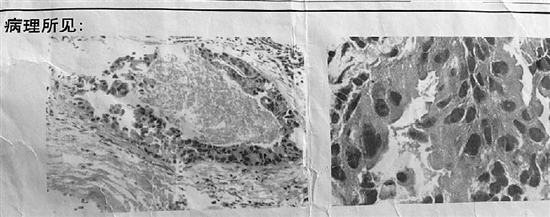

王越华毕业于法医专业,曾经从事司法鉴定工作。看了前后两张病理诊断报告,他觉得,从第一张病理图像看,确诊癌症复发没问题,很典型。但仅隔10来天,又诊断张女士没有复发是怎么回事?难道第一个病理诊断的样本不是张女士的?

在咨询杭州两家三甲医院的病理科医生时,对于第一张病理图像,两位医生的意见都一样:很典型,就是癌。但对比看了两张病理报告上的图像后,一位专家的想法与赵敏类似,另一位专家第一反应是,“不像一回事,这个会不会是别人的?”

他解释,第二张报告图像,看到的是类似鱼鳞的组织,跟张女士2015年的诊断相符;而第一张报告图像,更像腺癌。原来得了鳞癌,现在又得了腺癌,有这个可能性,但很小。倒是人为出错的可能性更大些。